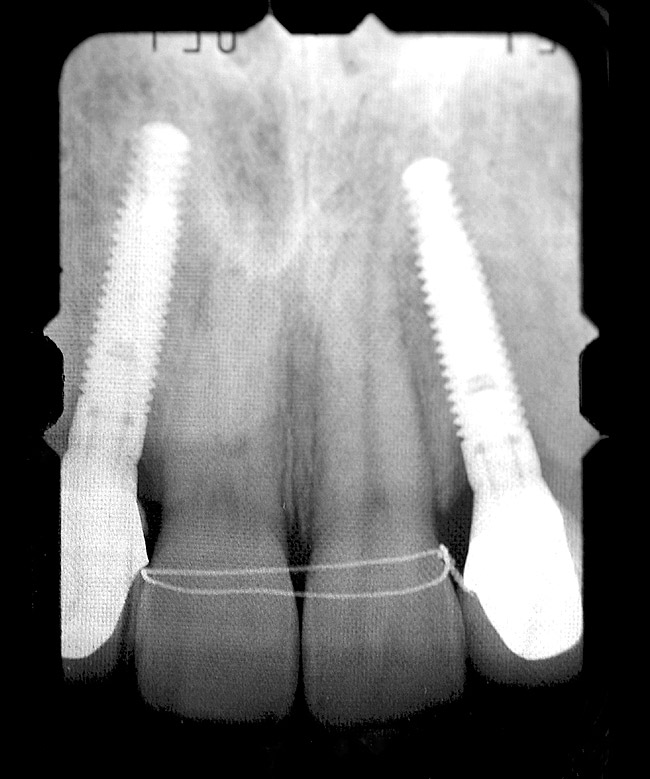

Figure 1  PRE-TREATMENT DIAGNOSTICS Pretreatment radiographs revealed convergent roots for the right canine and right central.

Figure 1

Periapical radiographs were taken to help determine the mesial-distal inclinations of the adjacent tooth roots (Figure 1). The radiographs revealed a serious issue, convergent roots for the right canine and right central, which eliminated that area as a potential implant-receptor site. The space between the left central and canine teeth was minimal, although the roots were relatively parallel. Clinical examination (manual palpation of the root eminences superiorly to the vestibule on the right side) confirmed the root convergence (Figure 2). The flat, wide zone of the keratinized tissue and lack of interdental papilla was evident for the missing right lateral incisor. There was a marked difference in clinical appearance for the left lateral, which could impact the eventual plan of treatment (Figure 3). Other significant clinical findings included bilateral facial bone concavities, which existed as a result of the congenitally missing tooth roots. As a diagnostic cue to the underlying bone topography, it is important to follow the demarcation between attached and unattached gingival tissue, and note the crestal width of the available keratinized tissue (Figure 4).